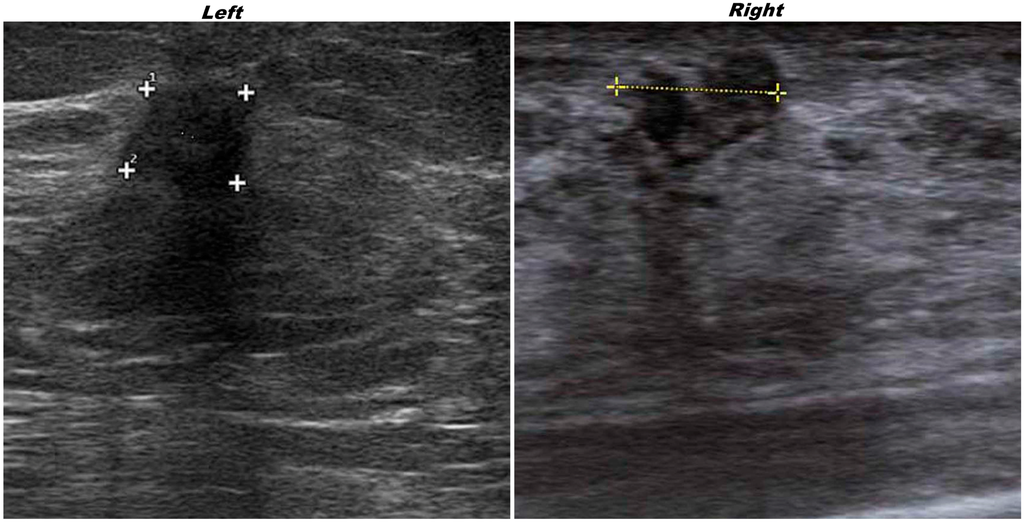

A 67-year-old woman, after a mammography with suspicious findings, was referred to our Institution. The ultrasonography revealed in the superior external quadrant of the left breast a solid hypoechoic mass of about 1.5 cm (Figure 1, on the left), suspicious for malignancy.

Figure 1. Ultrasonography of the left invasive ductal carcinoma(IDC) and right granular cell tumor (GCT) breast lesions. “Plus signs” underline the presence of suspicious lesions.

Ultrasonography on contralateral breast showed, in the upper inner quadrant, a solid hypoechoic oval mass of about 2 cm (Figure 1, on the right).